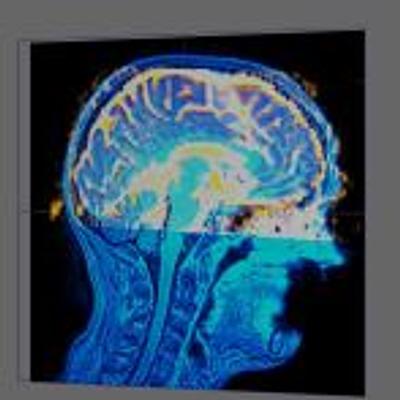

The surgical removal of brain tumors can lead to functional impairment. Therefore it is crucial to minimize the damage to important functional areas during surgery. These areas can be mapped before surgery by using functional MRI. However, functional impairment is not only caused by damage to these areas themselves. It is also caused by damage to the fiber bundles that connect these areas with the rest of the brain. Diffusion Tensor Images (DTI) can add information about these connecting fiber bundles. In this paper we present interactive visualization techniques that combine DTI, fMRI and structural MRI to assist the planning of brain tumor surgery. Using a fusion of these datasets, we can extract the fiber bundles that pass through an offset region around the tumor, as can be seen in Figure 1. These bundles can then be explored by filtering on distance to the tumor, or by selecting a specific functional area. This approach enables the surgeon to combine all this information in a highly interactive environment in order to explore the pre-operative situation.